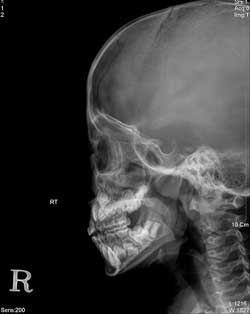

ÀÚ¼¼ÇÑ º´·Â ûÃë ÈÄ ±¸°, ºñ° ¹×

±ÍÀÇ ÁøÂûÀ» ÇÏ¿© ±¸°³Æíµµ, ÄÚÁ¡¸·°ú °í¸·ÀÇ »óŸ¦ Á¡°ËÇϰí X-¼± °Ë»ç·Î ¾Æµ¥³ëÀ̵åÀÇ »óÅÂ¿Í ºÎºñµ¿¿°(Ãà³óÁõ) µ¿¹Ý¿©ºÎ¸¦ °üÂûÇÑ ÈÄ Ä¡·á¹æÄ§À»

°áÁ¤ÇÑ´Ù. Çʿ信 µû¶ó¼ ¾Æµ¥³ëÀ̵åÀÇ À°¾ÈÀû °üÂûÀÌ ÇÊ¿äÇÏ¸é ºñµð¿À ÈÀ̹ö ³»½Ã°æ °Ë»ç¸¦ ½ÃÇàÇÒ ¼ö ÀÖ´Ù.